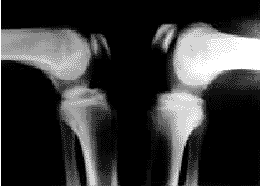

图1髌韧带长度左侧较右侧短缩6mm

6例(33%)患者髌韧带较健侧短缩。3例较健侧短1~3mm,2例短4~5mm,1例短6mm(图1),患侧髌韧带平均短缩2.8mm,相当于髌韧带长度(髌骨下极至胫骨平台水平面的长度)的8.5%。小切口关节切开术与关节镜下手术髌韧带长度改变差异无显著性意义(t检验,t=0.755,P=0.4)。